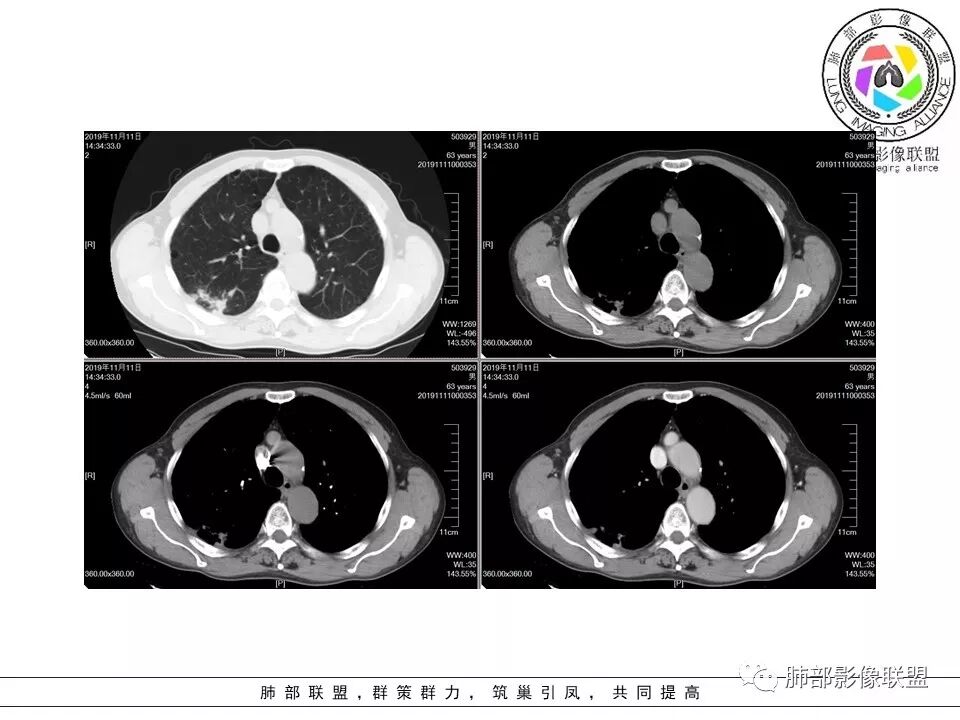

大雄:老年男性,有类风湿病史,长期服用激素,无阳性主诉CT示右肺上叶后段及左肺下叶基底段胸膜下多结节影,境界清晰,边缘毛糙,整体收缩,长轴与胸膜平行,增强扫描轻中度均匀强化。考虑炎性病变,建议查隐球荚膜多糖滴度试验

晕晕菜:患者中老年男性,体检发现肺部占位。既往既往有类风湿关节炎,长期口服激素胸CT:间隔旁肺气肿,右肺上叶后段胸膜下病变,与胸膜宽基底相连,局部胸膜明显增厚,病灶内可见空洞,病灶周围有散在卫星灶。左肺下叶背段胸膜下实变,病灶边界清楚,与长轴与胸膜平行,病灶周围可见软毛刺,纵隔窗可见病灶与胸膜呈糊墙征。 总体考虑良性病变。右上:结核?左下:隐球菌?

没意见:老年男性,明确有风免疾病背景,长期激素治疗,CT:双肺下叶外周多发结节,大部分宽基底胸膜相连,长轴垂直支气管,刀切平直,密度较为均匀,近心端空洞,强化程度目测略低,下肺背侧网格、磨玻璃、小蜂窝,考虑炎性结节,至于是感染还是风湿结节难度较大,需要结合临床来进一步确认

小赵:老年男性,类风湿及长期服药史。胸部CT所见右肺上叶及左肺下叶胸膜下多发病灶,右肺上叶病灶内见空洞及液平面,内壁光滑,周围散在条索及小结节样卫星灶,邻近胸膜增厚,增强扫描病灶轻度强化。左肺下叶病灶长轴平行于胸膜,周围见边界不清磨玻璃密度影,与邻近胸膜成糊墙改变。增强扫描病变成不均匀明显强化,内见强化血管影。诊断一元考虑双肺炎性病变,隐球菌可能。二元考虑右肺上叶结核,左肺下叶隐球菌感染,粘液腺癌待排。

俞丽:双侧胸膜下结节及斑片影,与胸膜平行,大部分周围有晕症,边界模糊,胸膜下脂肪间隙存在,边缘平直,有强化。老年女性,良性,考虑隐球菌感染

菲菲菲:男,63,体检发现肺占位,既往类风湿性关节炎13年,双肺胸膜下多发斑片及结节影,右肺下叶病灶内见偏心性小空洞形成,周围有卫星灶,胸膜增厚,左肺下叶病灶轻度强化,纵隔内无肿大淋巴结,考虑炎性病变。隐球菌鉴别结核

一米阳光:双肺胸膜下多发结节病影,小结节融合,病灶与胸膜面平行,垂直支气管,边缘模糊,晕征,支气管进入堵塞,内见小空洞,增强均匀强化。结合病史,有类风湿病史,考虑炎性肉芽肿,隐球菌感染。鉴别,结核建议,穿刺,隐球荚膜抗原检查

雪上一枝蒿(陈显静):右上肺病灶,似见周边卫星灶,空洞朝向肺门,考虑炎性病变,结核?左下肺结节长轴平行胸膜,强化后似有低密度影,隐球菌?二元论?。

破风5:胸部CT:右上叶胸膜下病变,与胸膜宽基底相连,累及胸膜,病灶内可见空洞,洞壁光滑,病灶周围有散在卫星灶。有类风湿激素口服历史,结核首先考虑。左肺下叶背段胸膜下实变,病灶边界清楚,与长轴与胸膜平行,血管伸入,纵隔窗可见糊墙征。考虑良性病变,隐球?总体,右上肺结核,左下肺隐球,CTD-ILD

流心明智:患者,老年男性,既往有类风湿关节炎,长期口服激素史。胸CT:间隔旁肺气肿,右肺上叶后段胸膜下病变,与胸膜宽基底相连,局部胸膜增厚,病灶内向肺门侧空洞,病灶周围卫星灶。考虑炎性病灶。左肺下叶胸膜下气肿背景边缘实变、边界清楚、有膨隆、滋养血管征,软毛刺、多结节融合、糊墙征。 总体考虑:良性病变,右上:结核?左下:隐球菌?左下鉴别Ca。

傅昌瑜:男,63,体检发现肺占位,既往类风湿性关节炎13年,RF升高,右下肺胸膜下结节,边缘多发斑片,右肺下叶病灶内见偏心性小空洞形成,相应层面胸膜增厚,左肺下叶两个结节,上面大点的结节位于胸膜下,似有支气管进入后截断,病灶轻度强化,病灶内见坏死区,纵隔内无肿大淋巴结。肺内病灶似乎不怎么类似,隐球菌应该是兄弟同心。肺内病灶考虑肉芽肿性病灶,有长期口服糖皮质激素史,首先考虑奴卡可能,鉴别隐球菌及结核这个妖怪。类风湿结节没有见过。

初学者:支持。。。类风湿关节炎,那么肺内表现的是间质性肺炎,这个没有问题。现在就是看这些结节和团块是什么。患者有哪些危险因素:1.类风湿关节炎:类风湿结节 2.因为激素治疗,熊大说激素就是小艾滋,那么会容易得得:隐球菌,结核,PCP等等。3.间质性肺炎本身就容易发生肿瘤。所以目前我们需要考虑得三个方向:类风湿结节,肉芽肿性炎,或肿瘤。三者鉴别

三个石头:胸膜下多发结节,右肺上叶内空洞。增强扫描强化不明显。考虑良性病变,1.有类风湿病史,首先考虑类风湿结节,位于胸膜下,可以有空洞符合。如果病人皮下有类风湿结节,更符合类风湿肺结节,穿刺可以确诊。2.病灶长轴平行胸膜,不排除隐球菌,建议查隐球菌夹膜。

果哣.:老年男性,有免疫抑制服药史,右肺上叶后段胸膜下一节结影,内有空洞靠近肺门,周围散在小叶中心结节,左肺下叶靠近胸膜一节结影,长轴垂直支气管,糊墙,轻度强化,考虑结核,隐球菌带排。